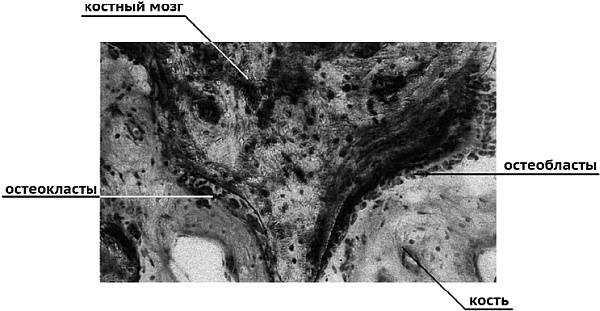

Остеопороз (от греч. osteon – кость и poros – поры) приобрел в западных странах эпидемические масштабы. Среди хронических болезней пожилого возраста в США он занимал в последние годы третье место, уступая лидерство сердечно-сосудистым и онкологическим заболеваниям. В Европе остеопороз пока еще не обогнал и диабет. По клинической картине остеопороз представляет собой медленную потерю костной ткани из-за диспропорций ее так называемого ремоделирования. Все внутренние скелетные кости имеют слой надкостницы, пронизанный капиллярами. В надкостнице на поверхности костей активны два типа клеток: крупные, многоядерные, и подвижные остекласты и мелкие, одноядерные, остеобласты. На каждый остеокласт приходится около ста остеобластов. Остеокласты локально разрушают костную ткань на поверхности кости, создавая мельчайшие углубления – лакуны. Мигрируя на соседний участок кости, остеобласты заполняют лакуны и начинают восстановительный процесс. Схема процесса показана на рисунке.

Срез костной ткани человека показывает остеокласты возле области костной резорбции и остеобласты, образующие новый слой кости [15].